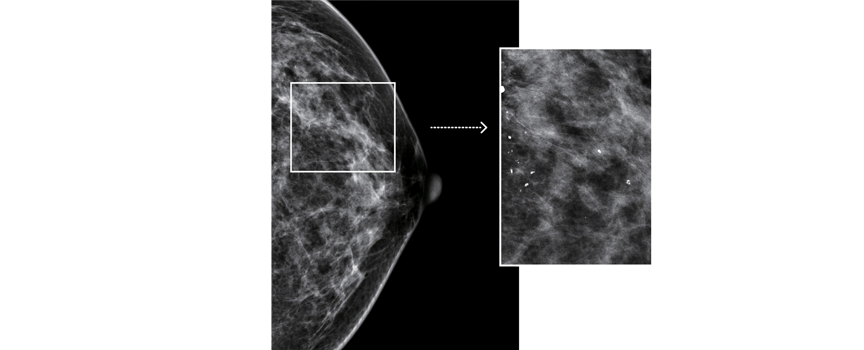

• Doskonała wizualizacja mikro-zwapnień – pixel o wielkości 76 µm.

Zaawansowany technologicznie system obróbki obrazu TRUVIEW® ART firmy DRTECH, dzięki technologi odwróconego filtrowania zdecydowanie poprawia ostrość otrzymywanych obrazów. Powoduje to zwiększenie prawdopodobieństwa wykrycia wszelkich zmian w tym także najmniejszych mikro-zwapnień.